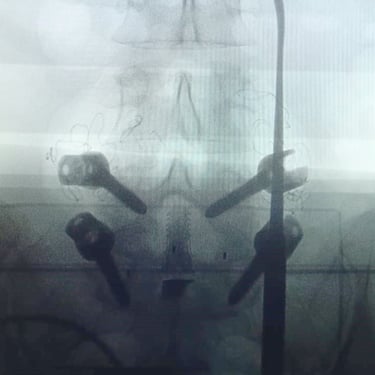

La cirugía ALIF (Anterior Lumbar Interbody Fusion), o Fusión Lumbar Intercorporal Anterior, es una técnica quirúrgica utilizada para tratar patologías de la columna lumbar como la degeneración discal, la inestabilidad vertebral o las hernias lumbares recurrentes. Mediante un abordaje anterior, se extrae el disco dañado y se coloca un injerto o caja intersomática que permite lograr la fusión estable entre las vértebras. Este procedimiento favorece una mejor restauración del espacio discal, alineación lumbar y preservación muscular. La cirugía ALIF es realizada por un equipo especializado en neurocirugía de columna, garantizando precisión y resultados funcionales óptimos.